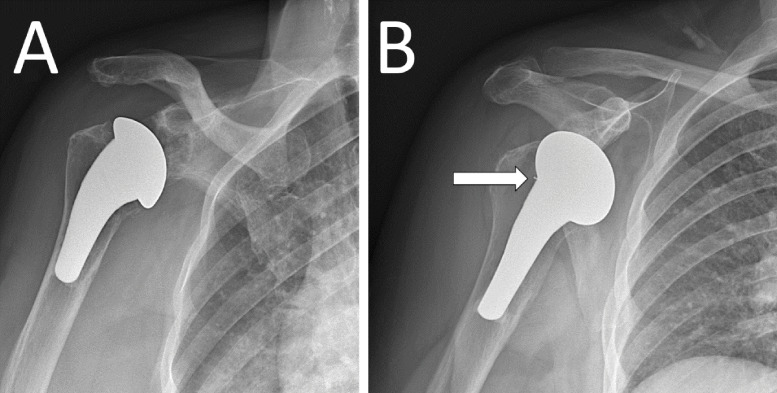

Glenoid component migration is a serious complication in total shoulder arthroplasty, causing 32% of failures and 7% of revisions. Detecting polyethylene loosening is challenging due to its radiolucency. We report a case of a 72-year-old woman with shoulder pain three years post-arthroplasty. Initial radiographs were unremarkable, but CT-arthrography revealed a displaced polyethylene spacer, rotated 90°, thus causing a mechanical block. Retrospective analysis of the X-rays showed the absence of the spacer in the expected position. Surgery restored functionality. This case highlights the diagnostic challenges of radiotransparent components with possible migration in unexplained post-arthroplasty shoulder pain. Teaching point: Verify glenoid component positioning in shoulder arthroplasties.